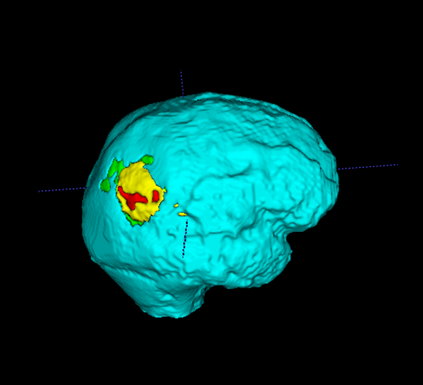

Segmentation of brain tumor from magnetic resonance imaging (MRI) is a vital process to improve diagnosis, treatment planning and to study the difference between subjects with tumor and healthy subjects. In this paper, we exploit a convolutional neural network (CNN) with hypercolumn technique to segment tumor from healthy brain tissue. Hypercolumn is the concatenation of a set of vectors which form by extracting convolutional features from multiple layers. Proposed model integrates batch normalization (BN) approach with hypercolumn. BN layers help to alleviate the internal covariate shift during stochastic gradient descent (SGD) training by zero-mean and unit variance of each mini-batch. Survival Prediction is done by first extracting features(Geometric, Fractal, and Histogram) from the segmented brain tumor data. Then, the number of days of overall survival is predicted by implementing regression on the extracted features using an artificial neural network (ANN). Our model achieves a mean dice score of 89.78%, 82.53% and 76.54% for the whole tumor, tumor core and enhancing tumor respectively in segmentation task and 67.90% in overall survival prediction task with the validation set of BraTS 2018 challenge. It obtains a mean dice accuracy of 87.315%, 77.04% and 70.22% for the whole tumor, tumor core and enhancing tumor respectively in the segmentation task and a 46.80% in overall survival prediction task in the BraTS 2018 test data set.